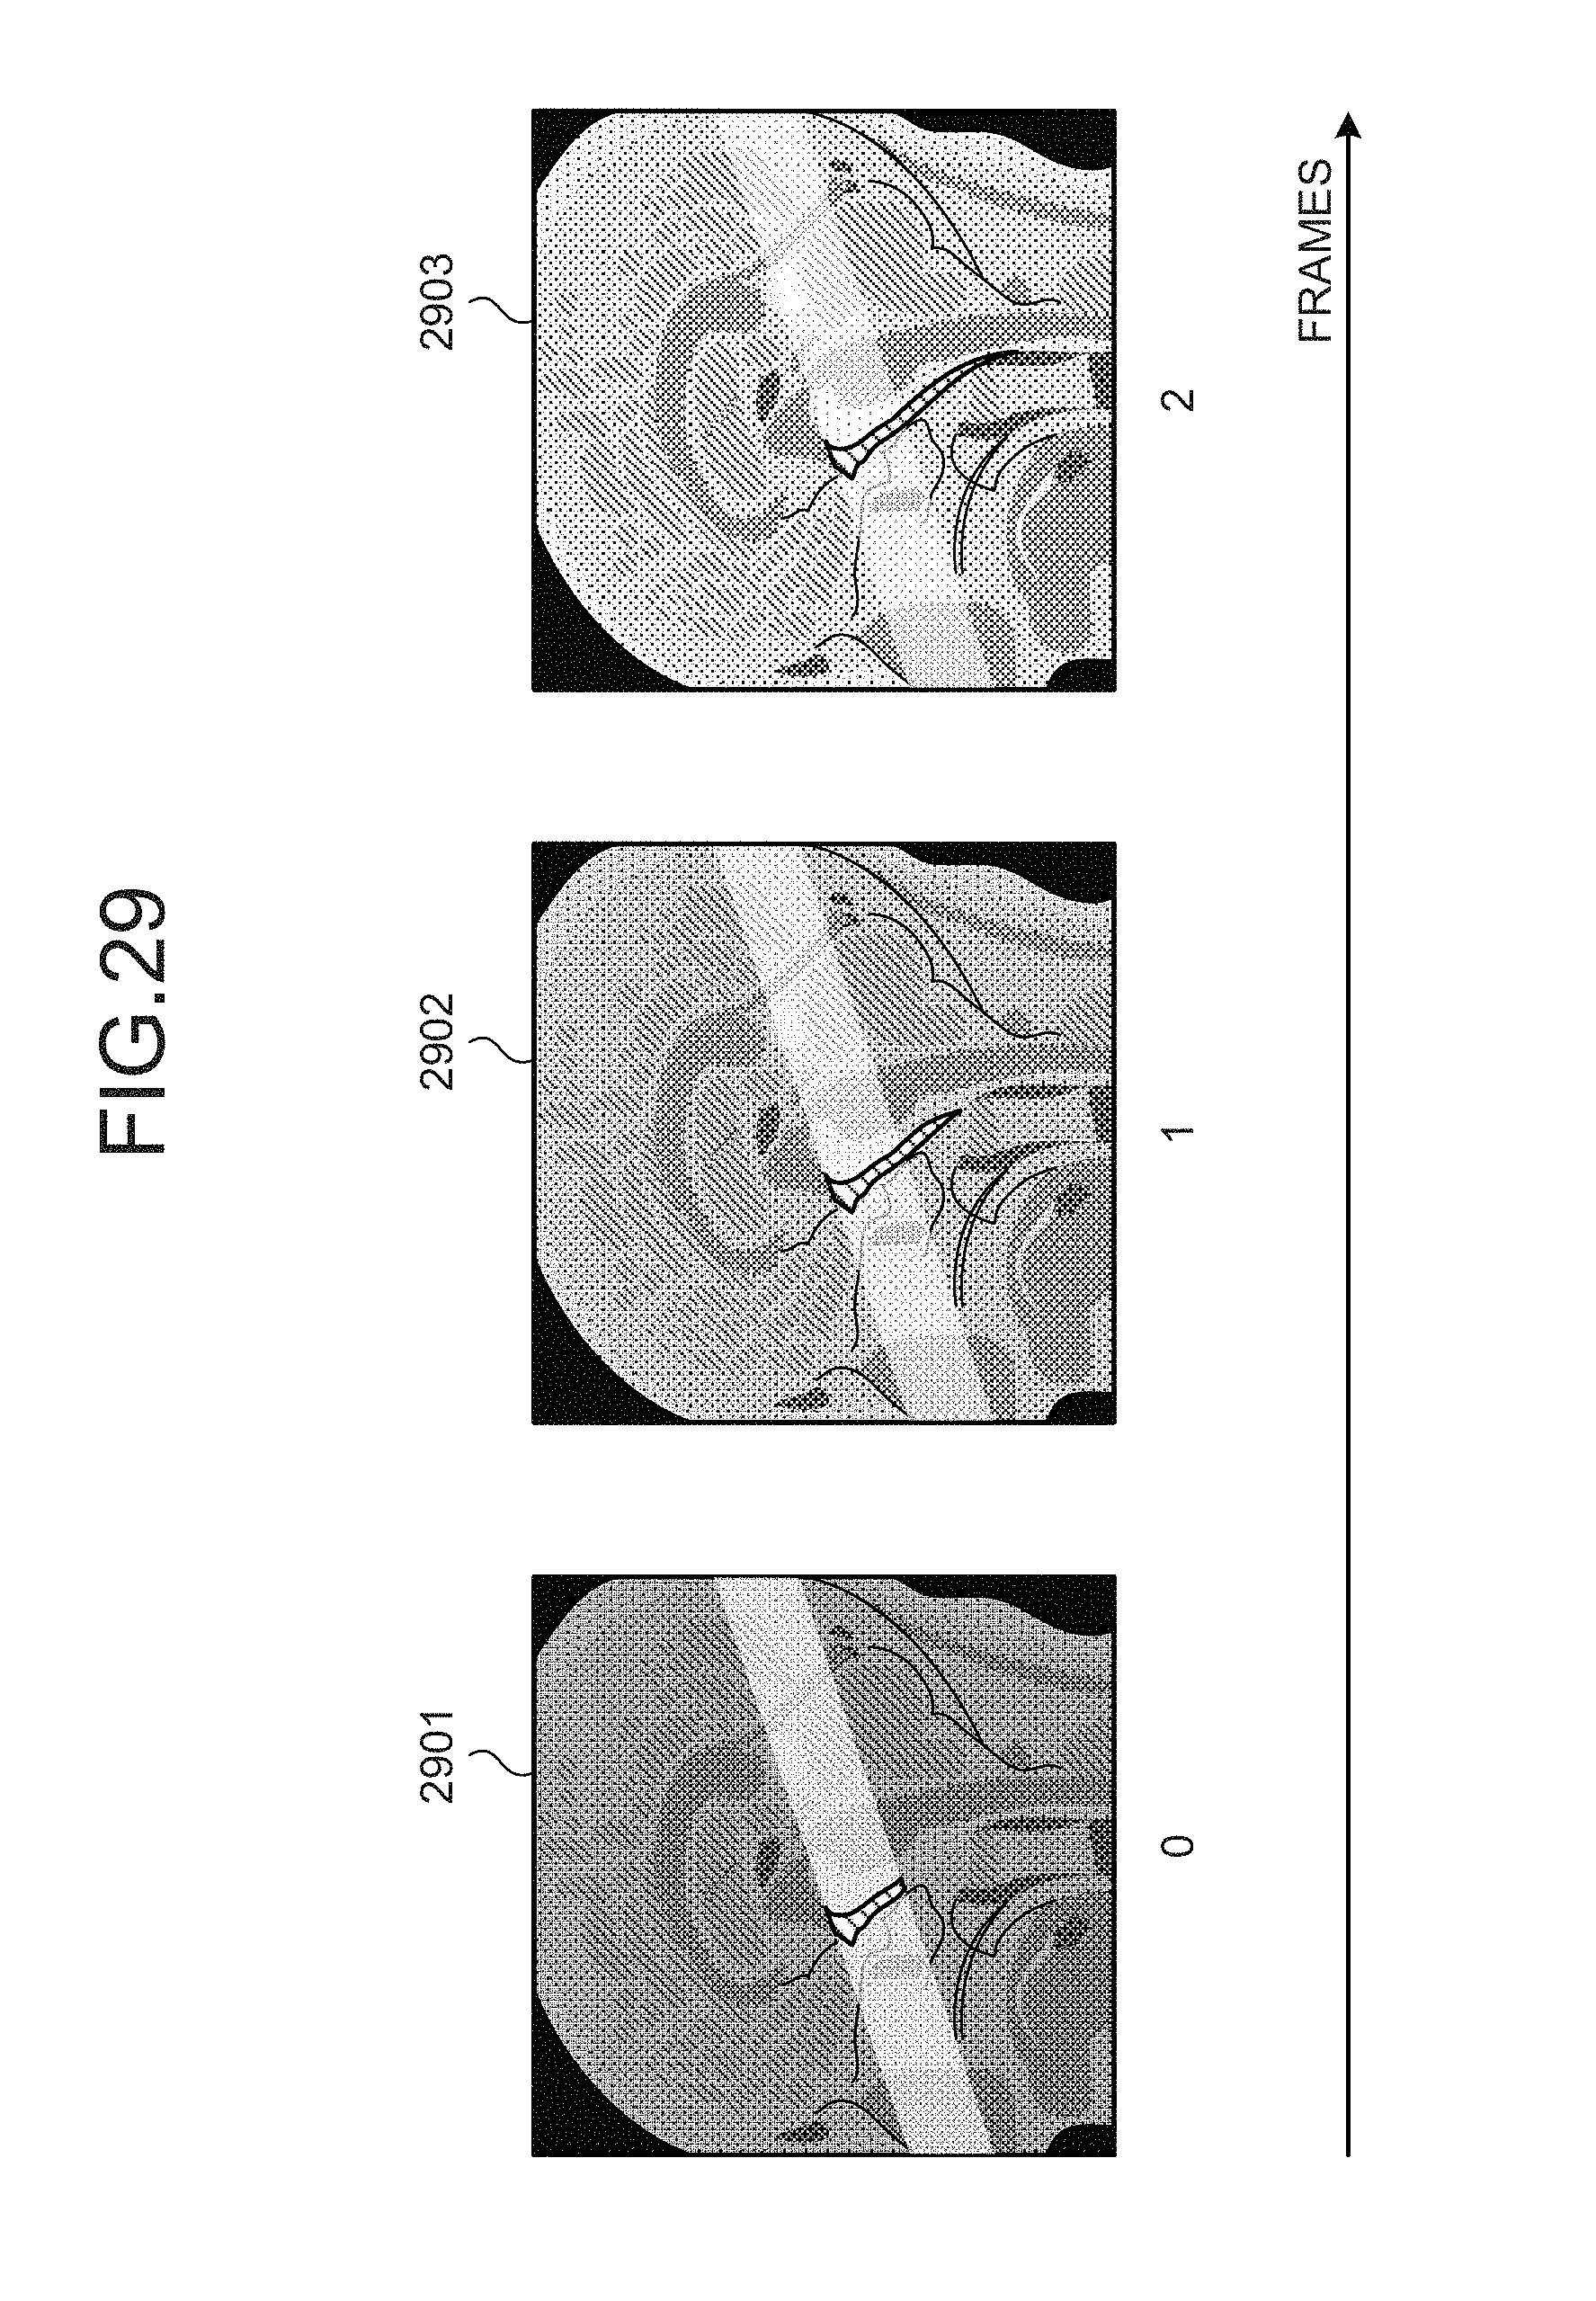

[0040]FIG. 29 is a drawing of exemplary displays according to yet another embodiment;